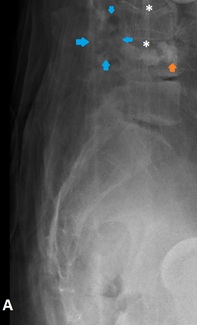

Foi realizada radiografia da coluna lombosagrada (figura 1), que revelou redução da altura dos corpos somáticos de L3 e L4, com sinais de cimentoplastia do corpo somático de L4 e discreto extravasamento de cimento para o espaço intradiscal L3-L4. Admite-se a presença de área de radiolucência em topografia das articulações interapofisárias de L3-L4 (setas azuis).

Figura 1: Radiografia lombo-sagrada na incidência de perfil (A), visualizando-se afundamento da plataforma somática superior de L3 e L4 (asteriscos) e presença de material radiodenso no espaço intervertebral L3-L4 no contexto de pós vertebroplastia (seta laranja). Discreta área radiolucente em topografia do maciço articular posterior de L3-L4 (setas azuis).